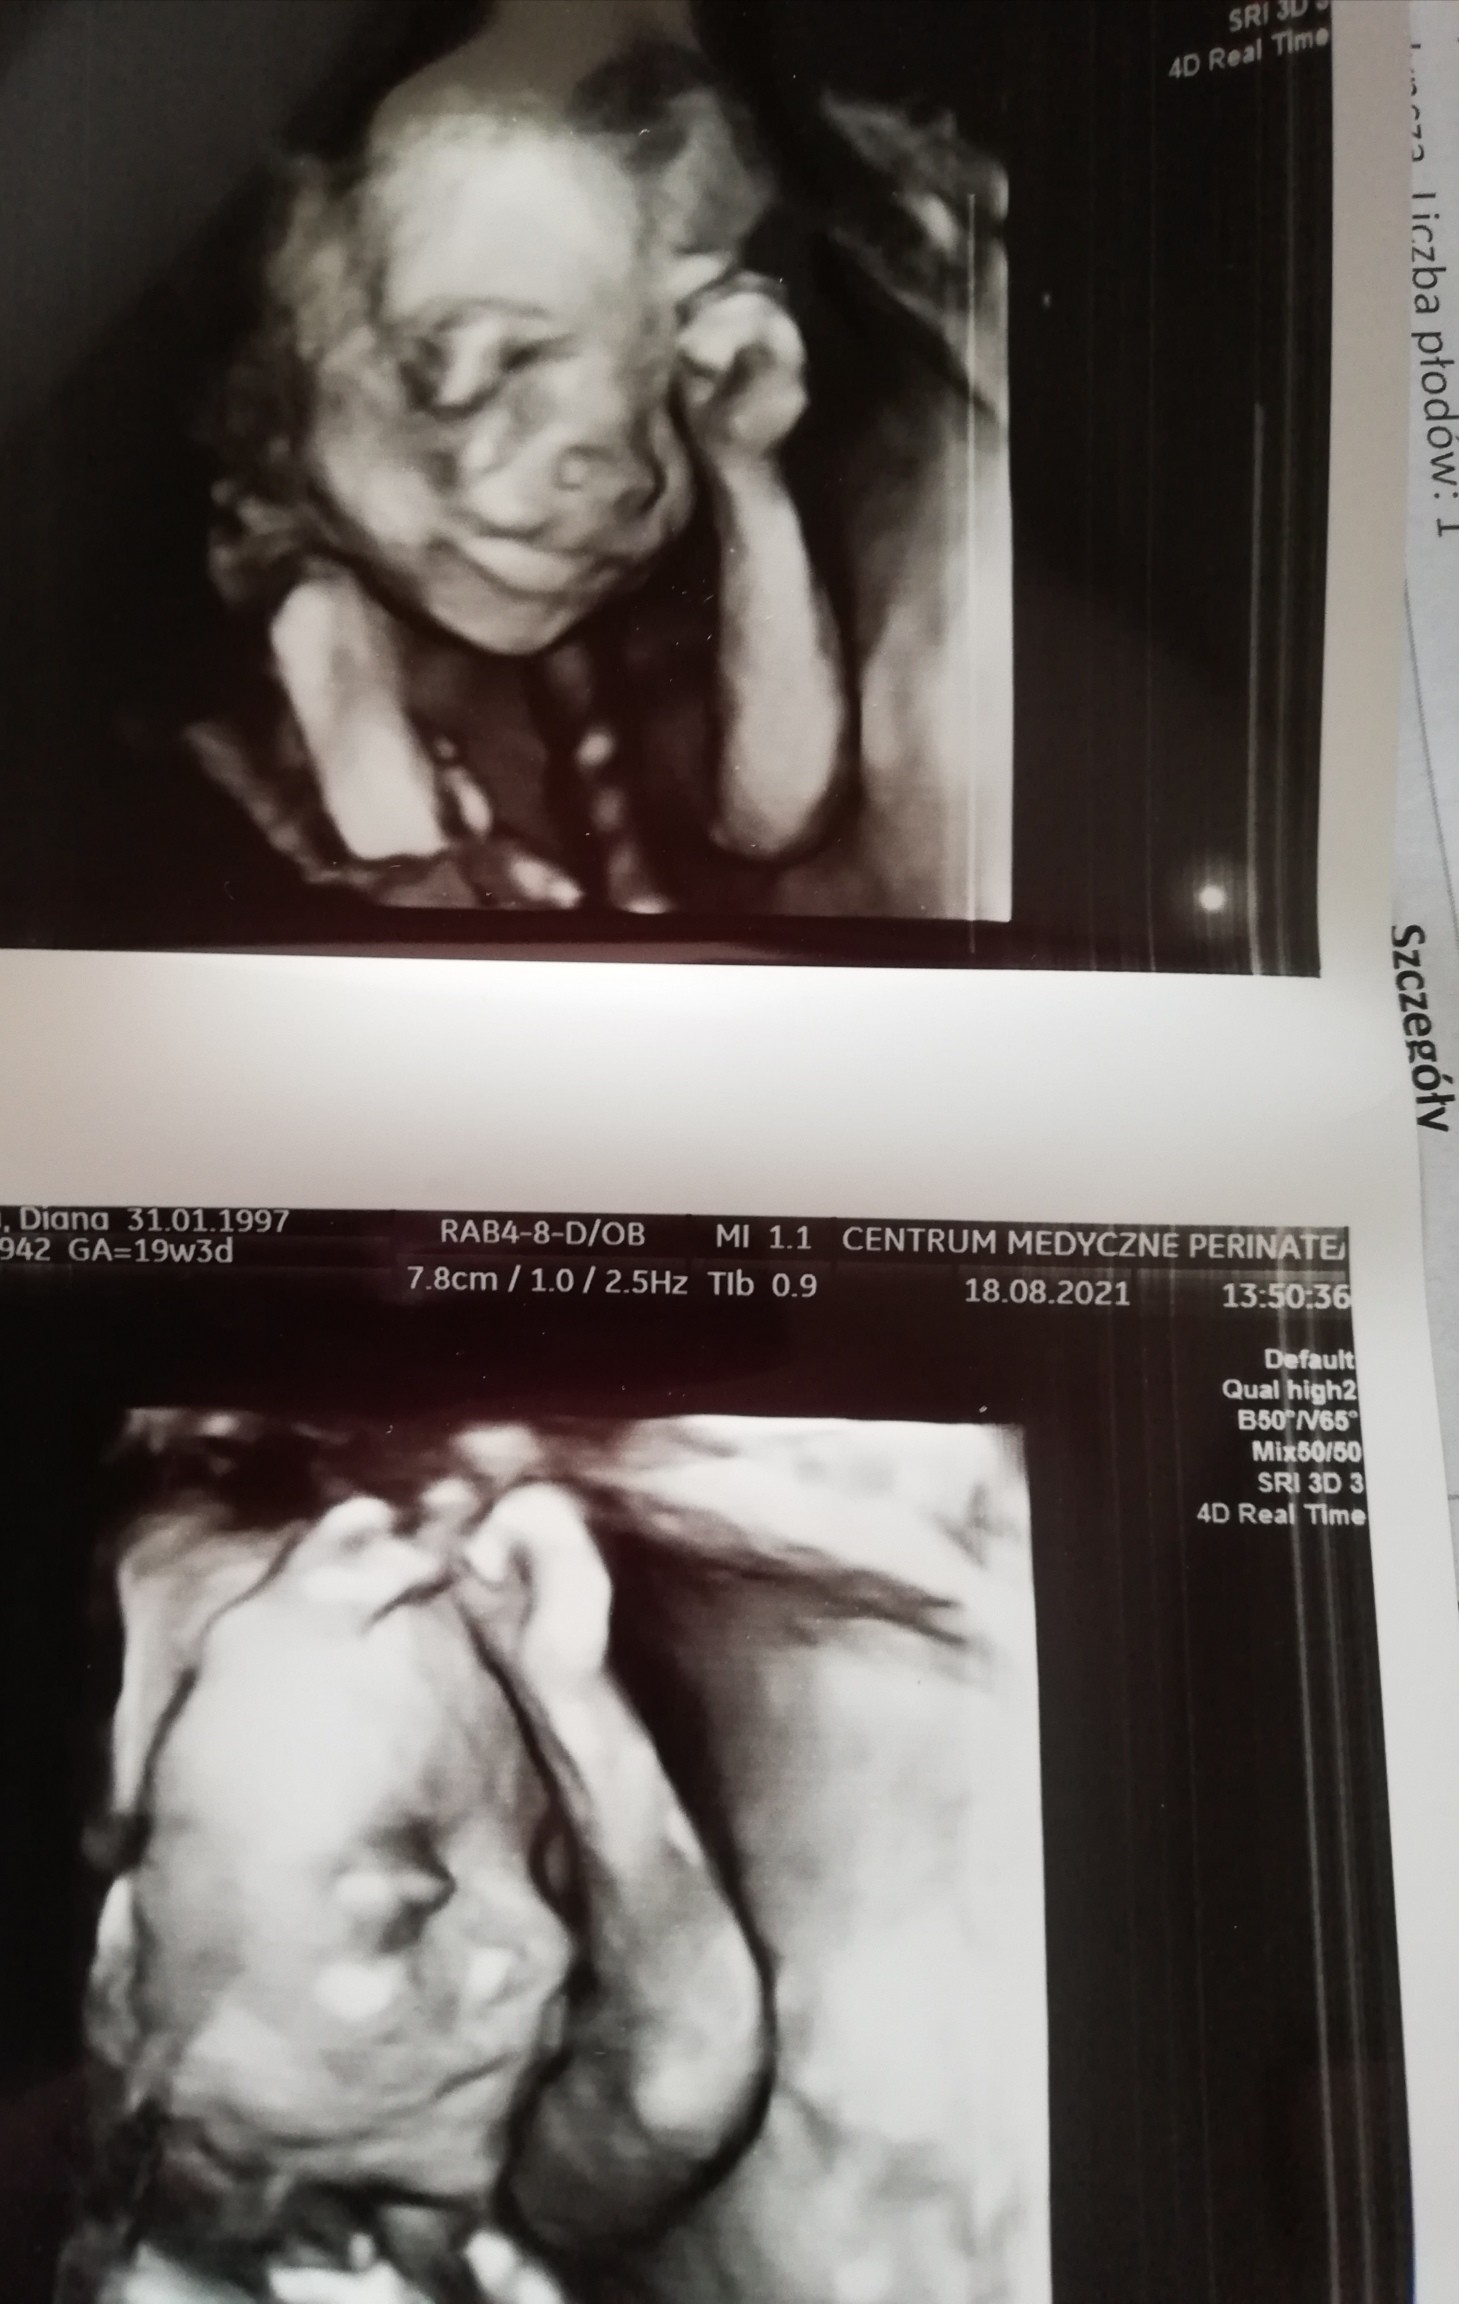

Ja to już czekam na połówkowe prenatalne, takie śliczne zdjęcie mam z synkiem i tak pięknie go było widać ❤️ pamiątka do końca życia ❤️

IMG_20210818_143005.jpg